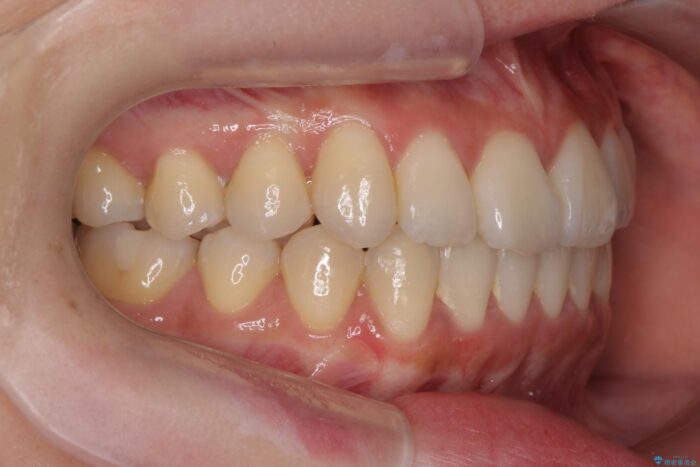

インビザライン +部分ワイヤー矯正

前歯のねじれが気になる、歯並びを改善したいとご来院された患者様です。

歯のねじれをきれいに取るのは、インビザライン(マウスピース矯正)だけでは難しい動きです。そのため、事前に4か月間の部分ワイヤー矯正を行い、治療期間を短くし、より美しい仕上がりを目指す計画です。

前歯が綺麗に並び、大変ご満足いただけました。